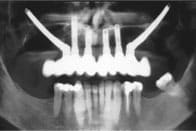

Zygoma start x ray tcm57 16556 tz6lj0 - Eugenol